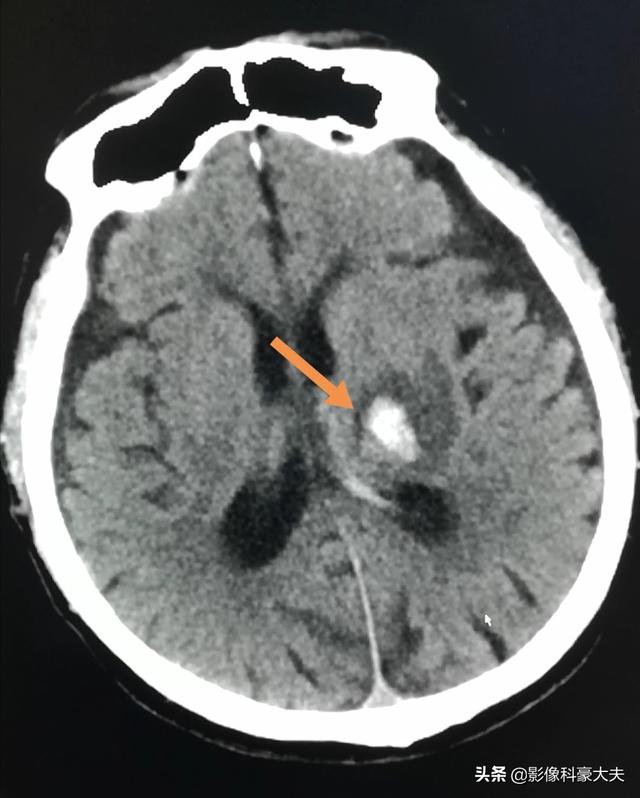

この患者(52歳)は、突然の頭痛で入院し、CTで左視床脳出血がはっきりと確認された。このような少量の出血であれば、通常は治療がよく、重篤な後遺症を残すことはない。